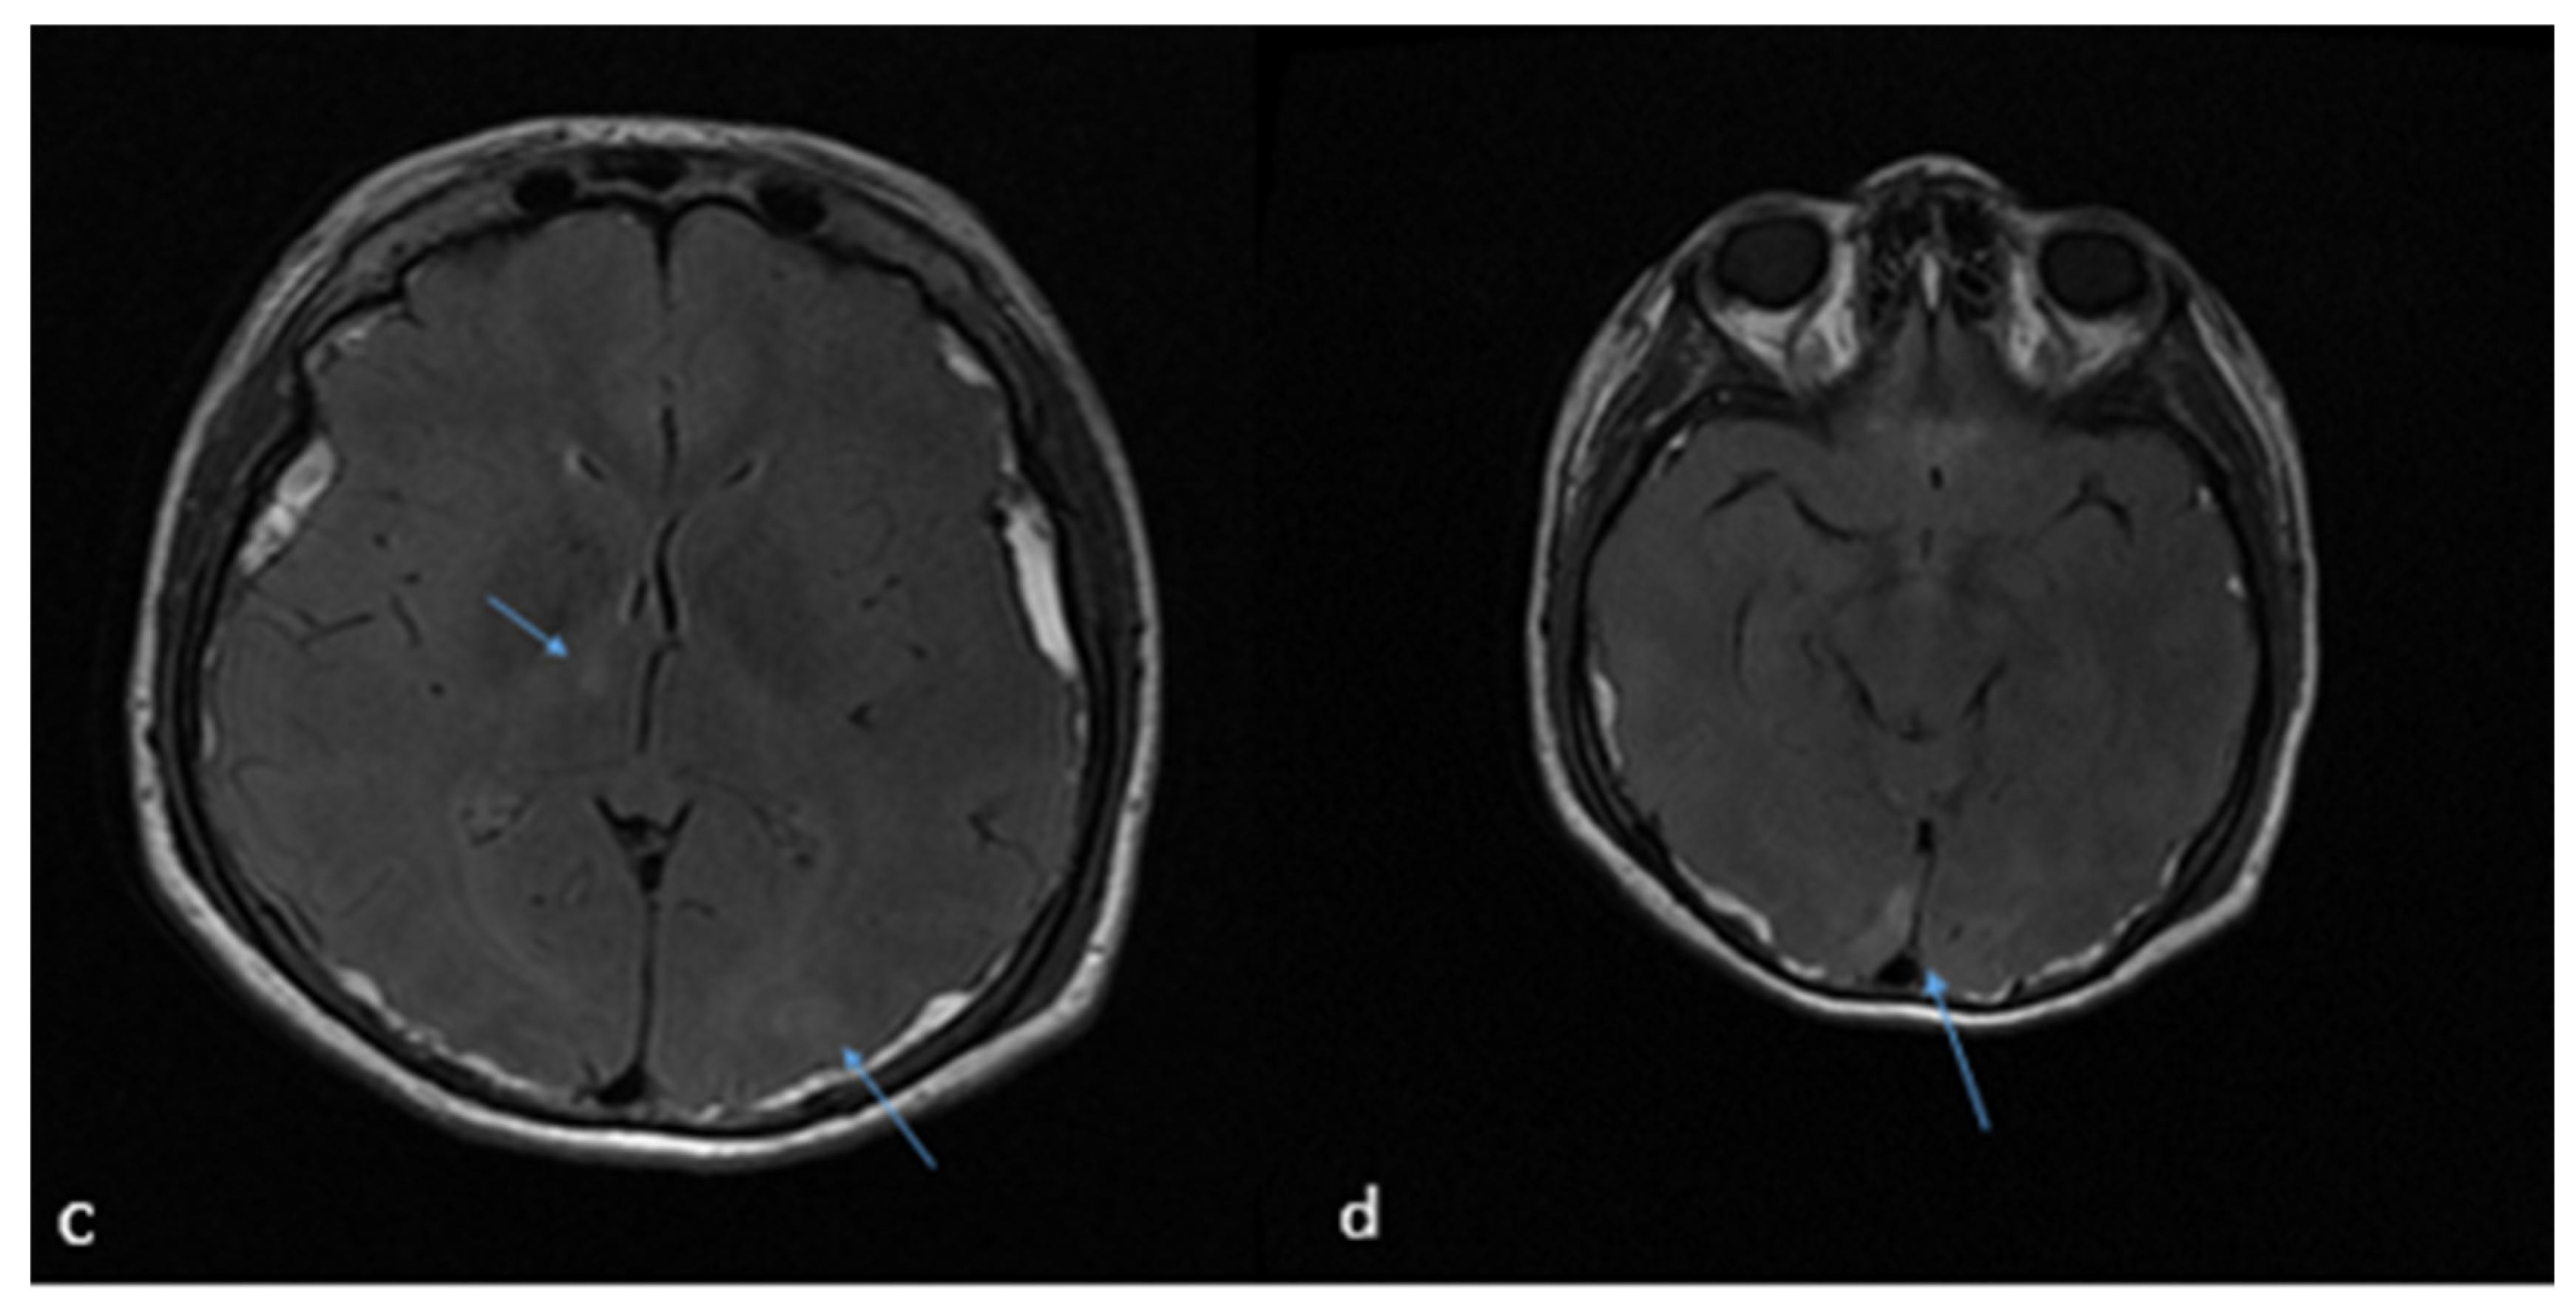

2. Case Report